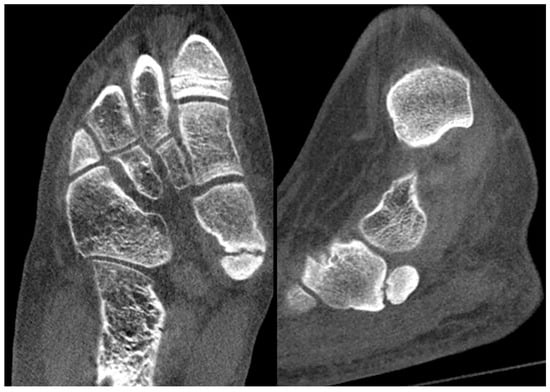

Standard radiographs and Computer Tomography (CT) scans commonly demonstrate a well-ossified accessory bone adjacent to the proximal medial margin of the navicular (Figure 17). In some cases, the accessory navicular is not only a source of localized symptoms but may also predispose the tibialis posterior tendon to chronic or acute injury. Tendinous fibers usually insert onto both the navicular and the accessory ossicle, and this atypical anatomy may increase the risk of tendon dysfunction, particularly in athletes. MRI in such individuals may reveal edema within the accessory navicular, indicative of chronic mechanical stress and overuse [63] (Figure 18).

Figure 17.

CT scan of a 12-year-old male patient showing a well-ossified accessory bone adjacent to the proximal medial margin of the navicular.